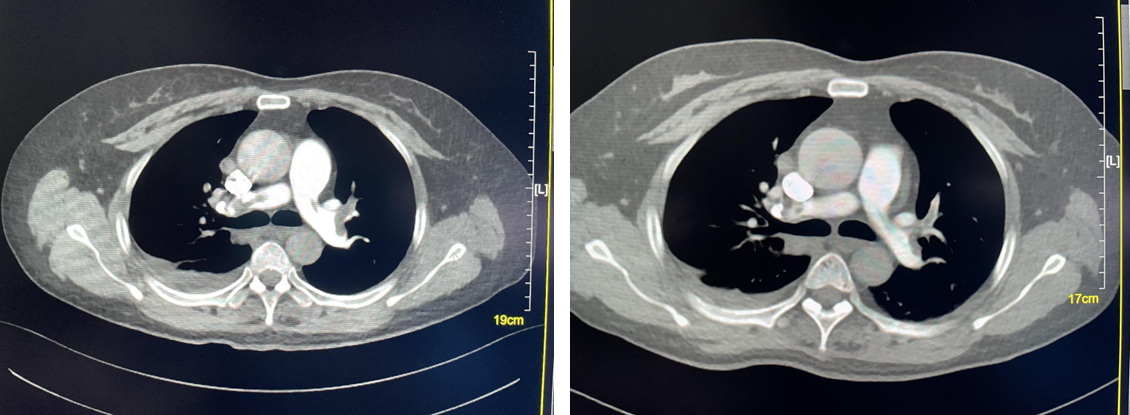

2023年2月,查胸部增强CT(图1)示:右肺下叶病变,伴部分肺实变,右侧肺门及纵膈内多发增大淋巴结,双肺多发磨玻璃结节。全身骨ECT(2022-03-03,图2)示:左6前肋骨代谢增高;T5、L5椎体骨代谢增高,结合病史提示骨转移。腹部CT、头颅MRI未见明显转移。

诊断方面,患者查胸部增强CT提示右肺下叶病变;全身骨ECT显示骨代谢增高,提示骨转移;腹部CT、头颅MRI未见明显转移。CT引导下经皮肺穿刺活检、超声支气管镜明确为肺腺癌,最终确诊为右肺腺癌(c-T2N2M1),基因检测提示TP53突变。